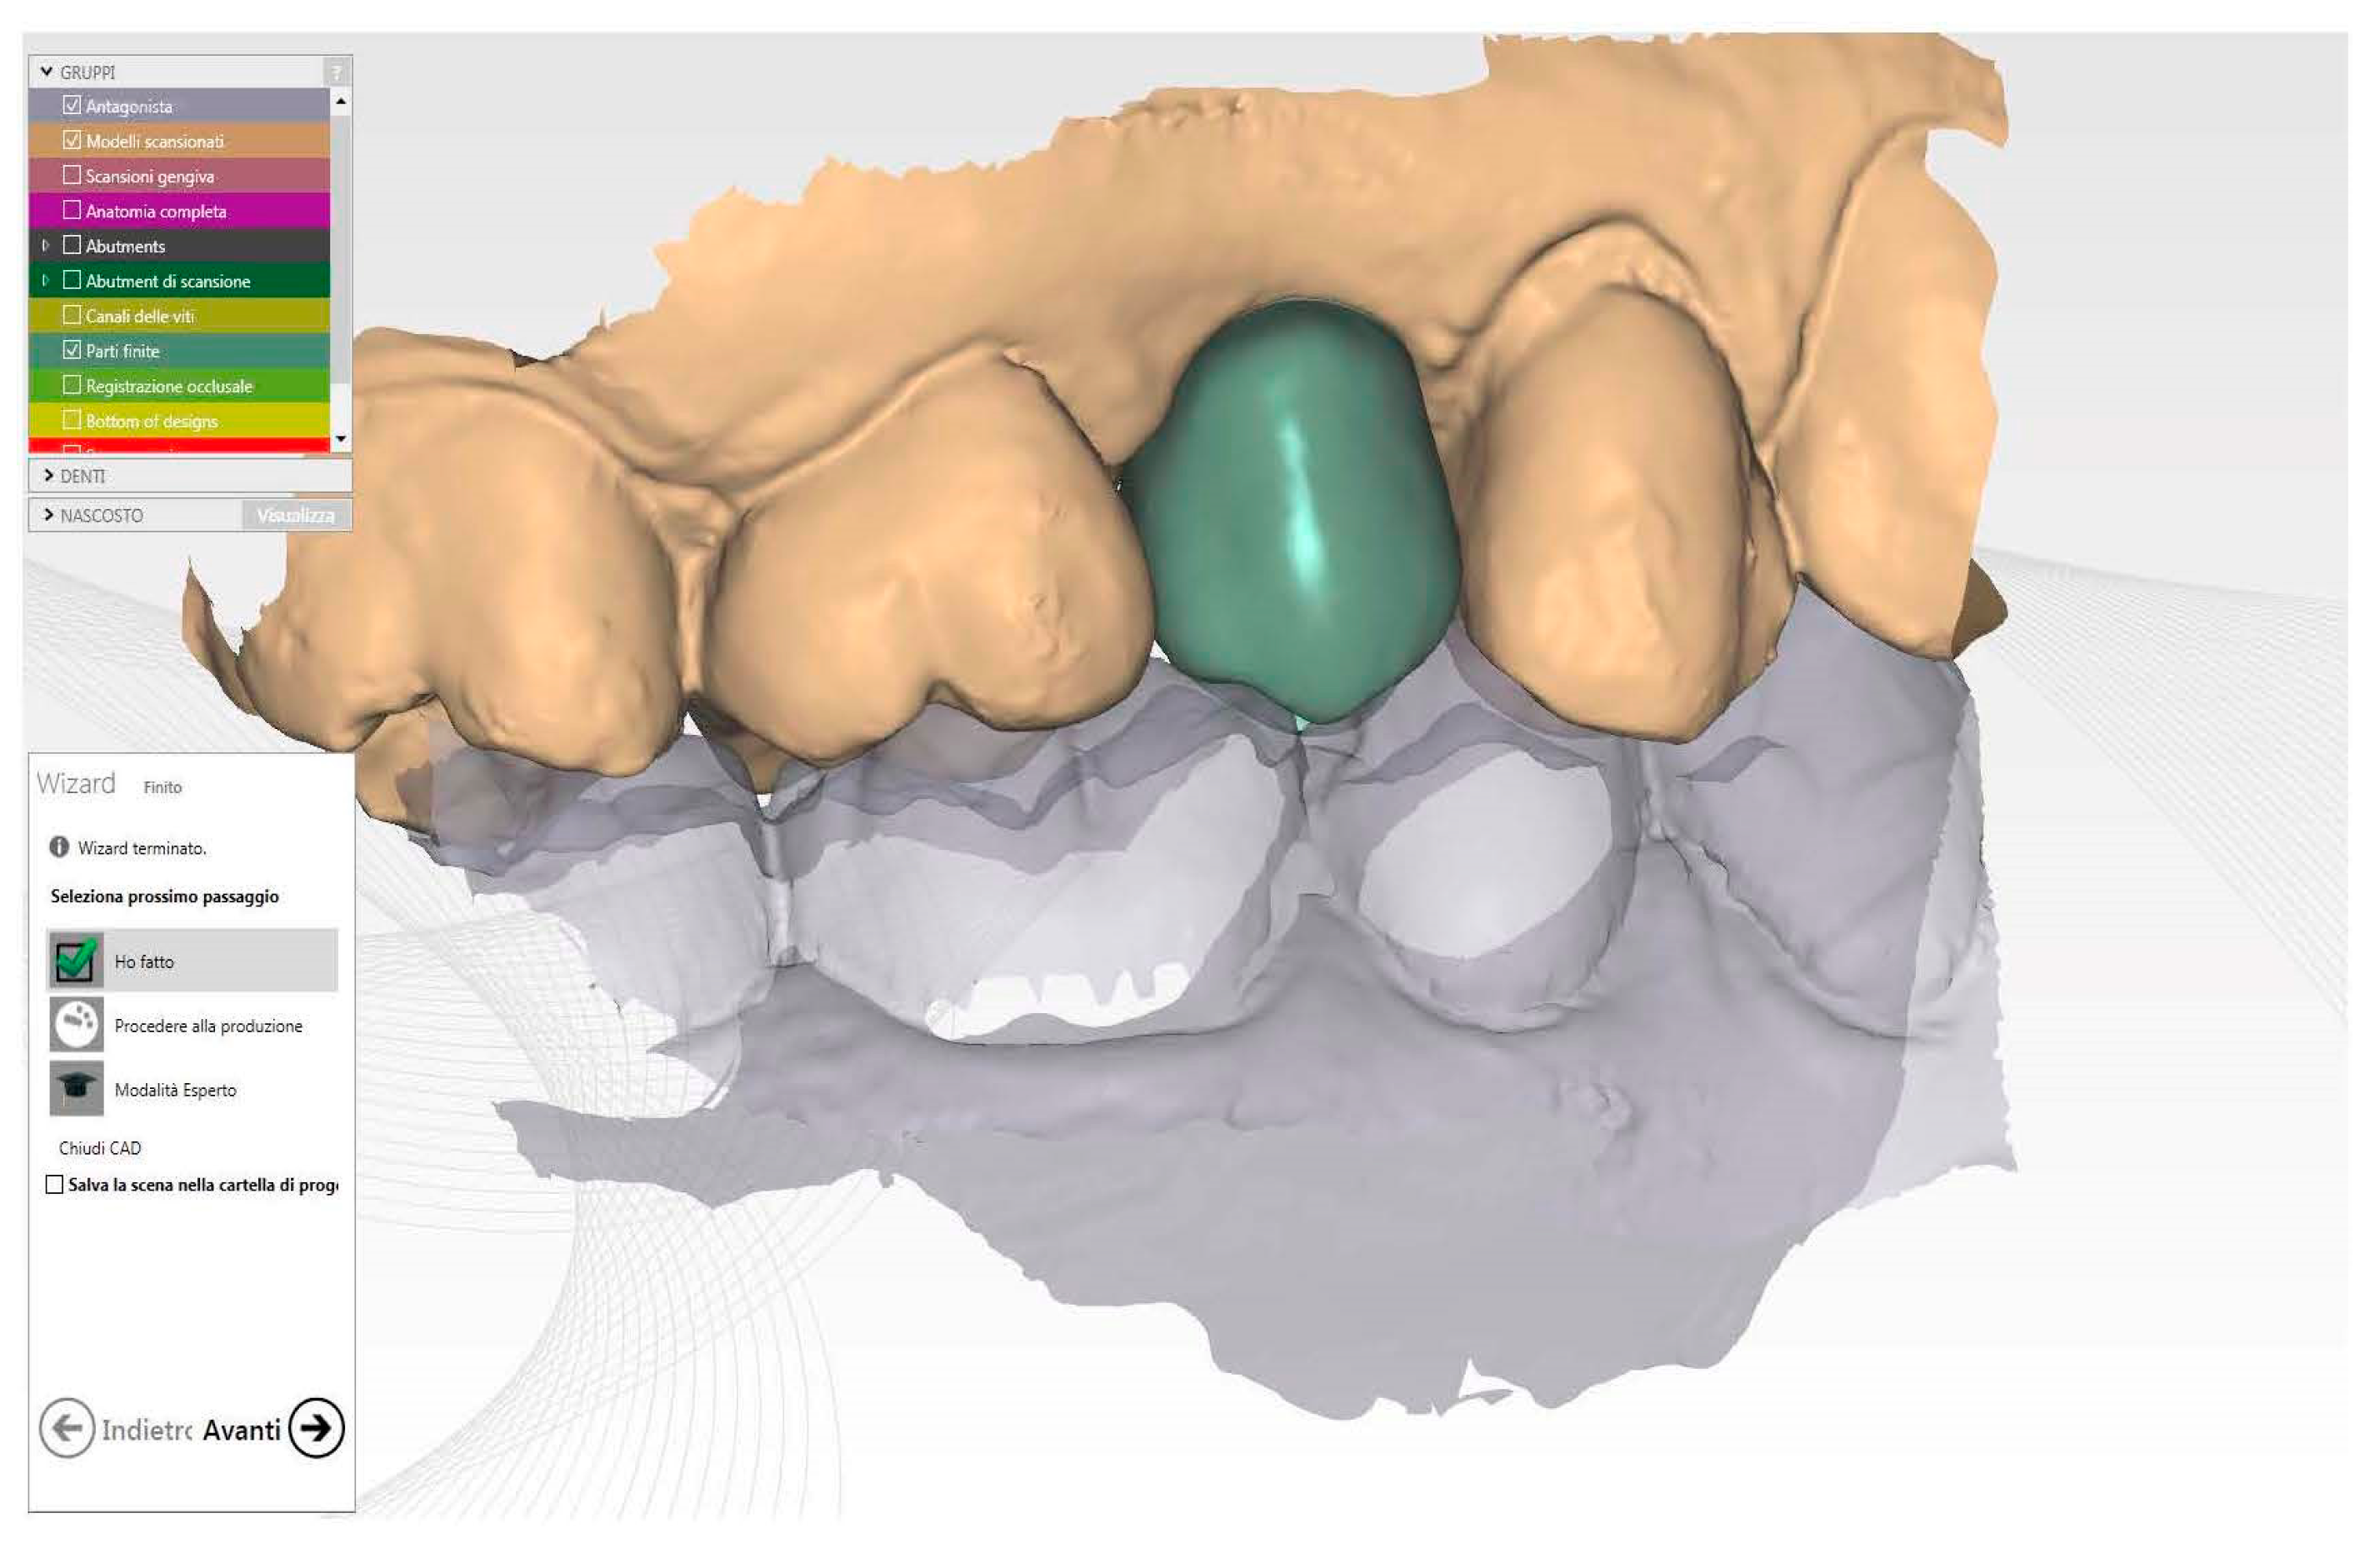

Figure 5.

Healing screw CAD modelling starting to future final crown shape.

To ensure the precise positioning of the implant, the intra-operative impression was utilized. The CAD software, using this crucial information, accurately positioned the virtual ti-base within the selected provisional, determining its ideal shape and orientation based on the correct coordinates. The finalized CAD file was then sent to a cutting-edge milling machine (Zfx Mill Inhouse X4, Zfx, Dachau, Germany) for fabrication. The healing abutment underwent a meticulous finishing and polishing process, taking great care not to interfere with the closure margins (Figure 6).

Figure 6.

Healing abutment in situ after implant insertion.

This attention to detail ensured precise fit and optimal soft tissue healing around the abutment.